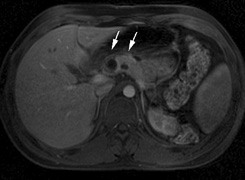

PANCREAS. Pancreatic lesions may be nonsecretory (most commonly cysts or cystadenomas) or secretory (islet cell tumor).179 In one study of 52 patients, 56% (29 patients) were found to have pancreatic lesions. The majority (19 of 29) had cystic changes only (Fig. 17C). Pancreatic lesions were the only abdominal manifestation of disease in 6 of 52 patients.180 In a separate study, pancreatic cysts did not show significant progression on follow-up examinations over an average period of 5 years.181 Like pancreatic cysts, islet cell tumors appear to be frequently asymptomatic.182 EPIDIDYMIS AND BROAD LIGAMENT. Papillary cystadenomas of the epididymis are typically benign and asymptomatic. In one study, about half of patients were affected.183 Papillary cystadenomas of the broad ligament are thought to be the female equivalent of papillary cystadenomas of the epididymis.184 OPHTHALMIC FEATURES VHL syndrome does not appear to have significant anterior segment manifestations. Posterior Segment Retinal capillary hemangiomas are among the most frequent and earliest manifestations of VHL syndrome. Most patients present between 10 and 40 (mean age of 25) years of age and 5% present before age 10. Overall, retinal capillary hemangiomas affect about 60% of individuals with VHL syndrome. Development of new retinal capillary hemangiomas after age 60 years is unusual.169,170 Retinal capillary hemangiomas (Fig. 18) may be the only manifestation of the syndrome,185 and typically involve the midperipheral temporal retina.186 A pair of dilated and tortuous retinal vessels (artery and vein) classically supply the vascular tumor. Without fluorescein angiography, it may be difficult to distinguish artery from vein on fundus examination.170